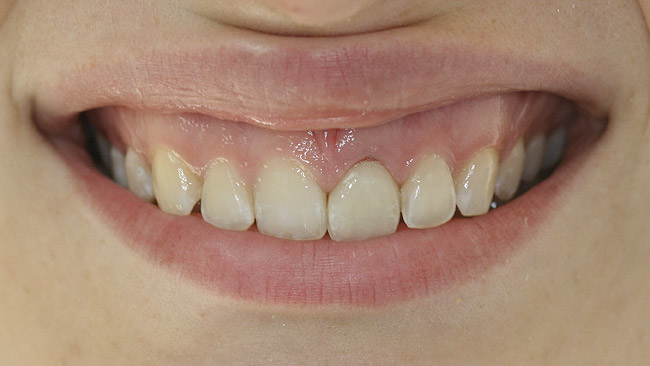

This patient faced a unique situation, perhaps not previously reported: retaining a healthy mandibular lateral incisor knowing this would create an esthetic compromise. Indeed, while the discrepancy in gingival-margin height is noticeable in retracted view (Figure 7), it does not show in full smile (Figure 8).

Figure 8  Full smile—finished feldspathic crowns on teeth Nos. 22, 23, 27, and 28; implant crowns in sites 24 through 26; esthetic harmonization with opposing dentition.

Figure 8